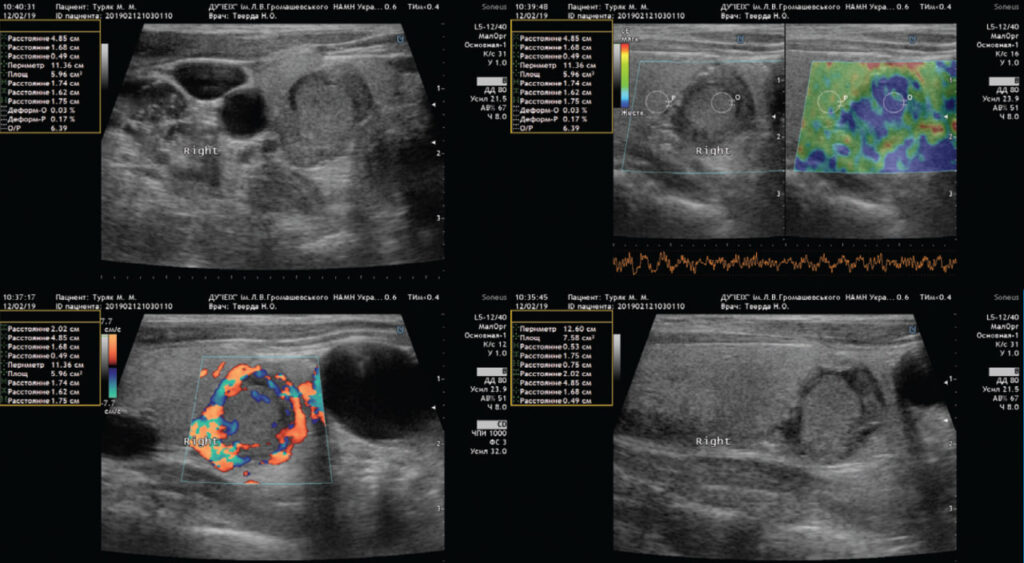

Компресійна еластографія використовується для дослідження вогнищевих утворень щитоподібної залози, молочної залози та новоутворень м’яких тканин.

При захворюваннях щитоподібної залози (вузловий зоб, гіпертиреоз, дифузні зміни, аутоімунний тиреоїдит) еластографія може бути використана для виявлення і розпізнавання на ранній стадії злоякісних і доброякісних утворень, що розрізняються в кілька разів своєю жорсткістю і для прийняття рішення про необхідність проведення біопсії.

Методи компресійної і зсувнохвильової еластографії можуть застосовуватися як додатковий засіб разом з мамографією та УЗД для діагностики злоякісних і доброякісних утворень молочних залоз при таких захворюваннях: кісти молочних залоз, фіброаденома, фіброзно-кістозна мастопатія. На відміну від мамографії еластографія не має обмежень по кількості досліджень через рентгенівське опромінення.